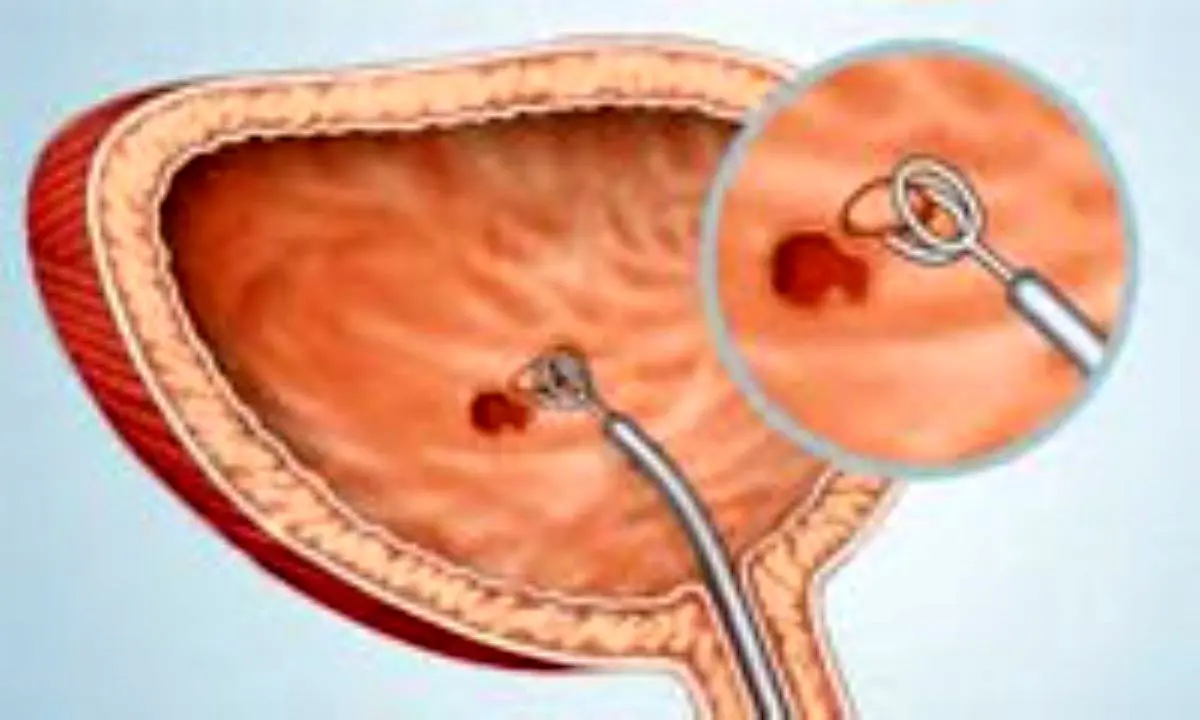

اگر مشکل مثانه دارید حتما این مطلب را بخوانید!

مطالعهای که در مجله سلامت، جمعیت و تغذیه منتشر شده است، نشان میدهد که OBS - وضعیتی که با میل ناگهانی و مکرر به ادرار کردن، که گاهی اوقات با بیاختیاری ادرار همراه است - مشخص میشود، به طور قابل توجهی بر کیفیت زندگی تأثیر میگذارد و با افزایش سن، به ویژه در زنان، شایعتر میشود.